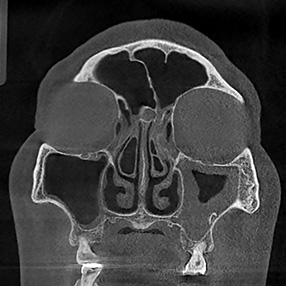

※ 축농증 수술 후 생길 수 있는 부작용으로는 출혈, 감염, 염증이 있을 수 있습니다.

본 사진은 의료기관에서 진료를 본 환자이고, 전후 사진 인물이 동일인이며,동일조건에서 촬영이 되었습니다.